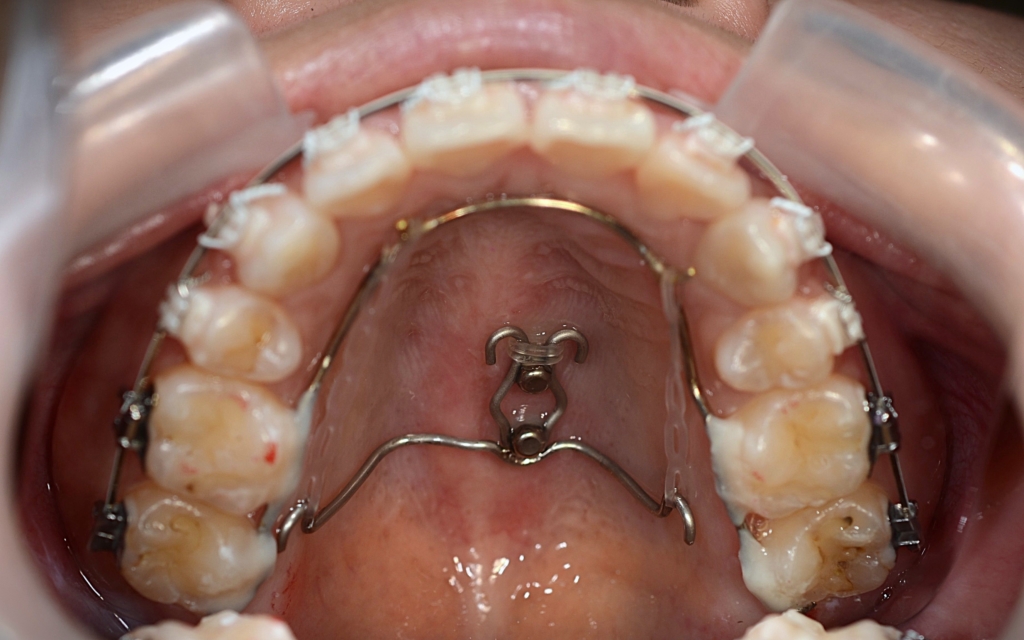

そこで、アンカースクリューを追加して更に引っ込めることにしました。

上顎の口蓋の中央部に2本植立しました。

上顎のアンカースクリューにはPLAS & 奥歯の内側にはパラタルバーを付けて、上の歯列(歯並び全体)を出来るだけ後方へ引っ込めて行く「矯正力」を加えて、治療を再開しました。